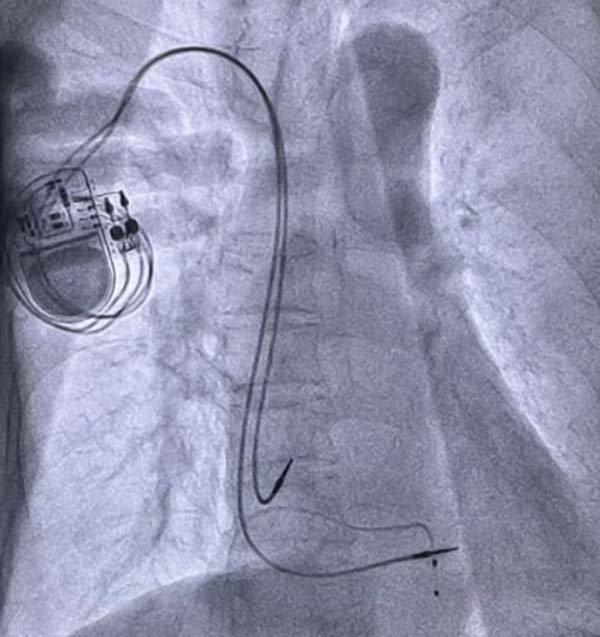

最终,团队成功将双主动电极精准植入理想位置,通过双主动电极间隔部起搏模拟生理性起搏,最大程度贴合心脏正常电传导节律,减少心肌损伤。整个手术过程精准流畅,起搏参数全部达标,术后患者恢复顺利,晕厥、头晕等症状彻底消失,此次手术的成功,充分彰显了我院心血管内科团队的精湛技术与责任担当,标志着科室在复杂高危心律失常诊疗领域再获突破。